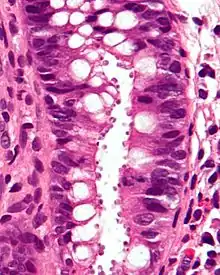

| Micrograph showing cryptosporidiosis. The cryptosporidium are the small, round bodies in apical vacuoles on the surface of the epithelium. H&E stain. Colonic biopsy. | |

Other staining techniques include acid-fast staining,[26] which will stain the oocysts red.[25] One type of acid-fast stain is the Kinyoun stain.[21] Giemsa staining can also be performed.[22] Part of the small intestine can be stained with hematoxylin and eosin (H & E), which will show oocysts attached to the epithelial cells.[25]